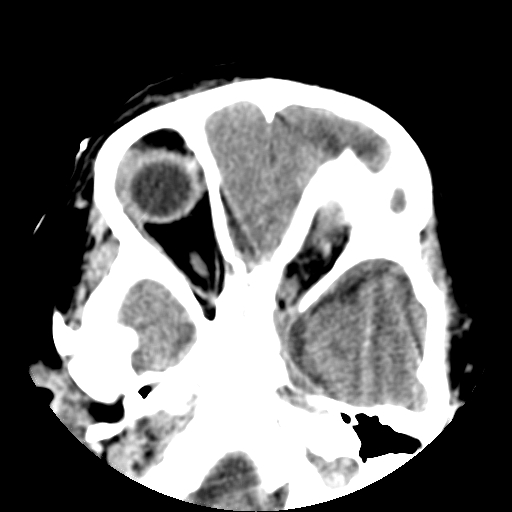

以下是引用深泽交通医院在2009-10-16 8:25:00的发言:[br]右眼环出血伴异物

以下是引用卜一在2009-10-16 15:01:00的发言:[br]右眼球挫裂伤伴异物!

以下是引用拾荒者在2009-10-17 18:38:00的发言:[br]鼻面部皮下积气,右侧睑缘及眼球壁高密度异物影,左侧眼球壁晶状体内侧缘处是圆形低密度影。低密度异物?应提请眼科医生注意。